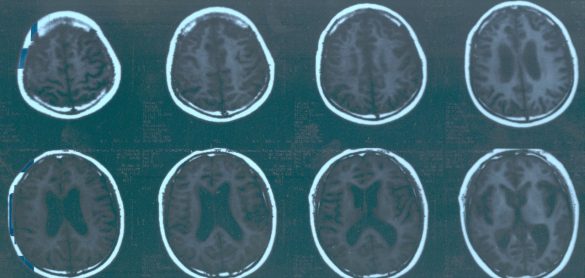

而是脾气变得很不好,一会烦躁不安,一会儿又情绪低落抑郁,大家都以为他是太累了,单位安排他去一个清净的地方疗养。疗养期间,有一天他正与一个来看他的学生下棋,突然之间就昏倒在棋桌上。救护车送到医院后做了一个全脑CT检查,结果发现脑子大面积发炎(见上图),这么大面积的炎症,医生给注射了大量抗生素,可是出乎所有人意料炎症一点没有消!

激素一上立竿见影, 接下来的CT检测就看到脑子里的炎症已经消减! 原来CT片子因炎症都变白了,现在居然正常了! 脑子里的炎症消了,身体其他部位本来就没有问题,人很快就恢复正常并且出院了。回去以后爸爸常说的一句话就是:太感谢麻省总院了, 真是神了,一用药就好了,真是神了!也感谢王主任,要不是他懂英语,也没法和麻省总院合作呀!